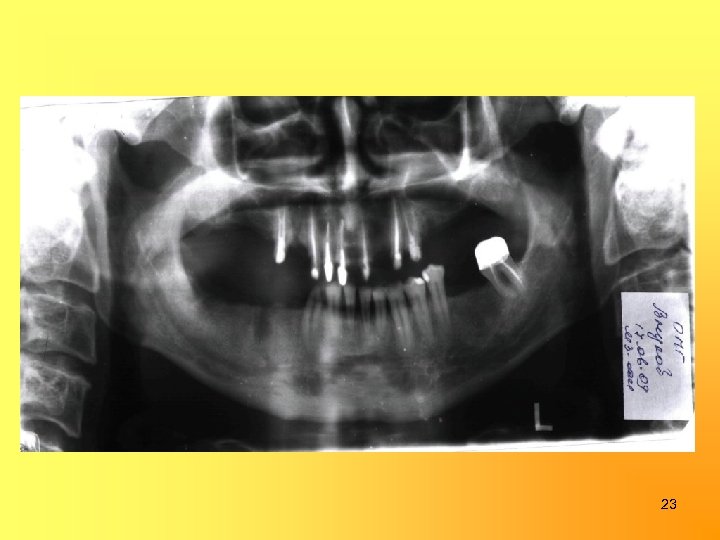

23

8

Одонтопародонтограмма 0 0, 9 0 1, 1 0, 7 0, 9 0 1, 1 0, 9 0 0 0 ½ 0 ¼¼¼¼ 0 ¼½ 0 0 0 0 8 7 6 5 4 3 2 1 1 2 3 4 5 6 7 8 0 0 0 ¼½½½½¼¼¼ 0 ½ 0 0 1, 3 0 1, 1 0 1, 5 0 0, 5 0, 5 1, 1 1, 3 9